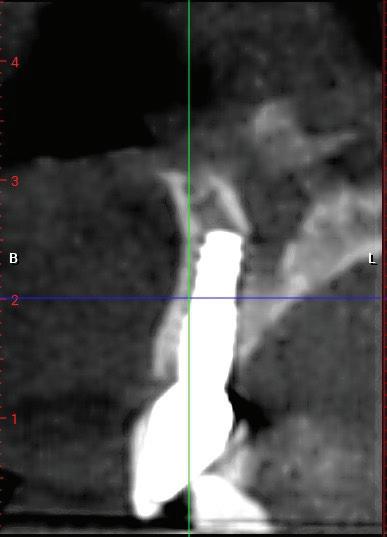

SITE AUGMENTATION Reconstituirea țesutului moale periimplantar și papilar în zona estetică

RECONSTITUIREA țesuturilor moi periimplantare. Scopul acestui raport de caz este de a demonstra procedurile chirurgicale utilizate pentru corectarea unui defect al țesuturilor moi periimplantare folosind țesutul moale interdentar în combinație cu tuberozitatea ca locație donatoare de țesut conjunctiv, utilizând o abordare prin tunelizare într-o zonă estetică.